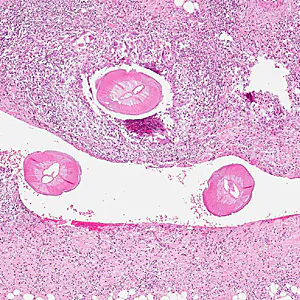

DPDx is an educational resource designed for health professionals and laboratory scientists. For an overview including prevention, control, and treatment visit www.cdc.gov/parasites/.